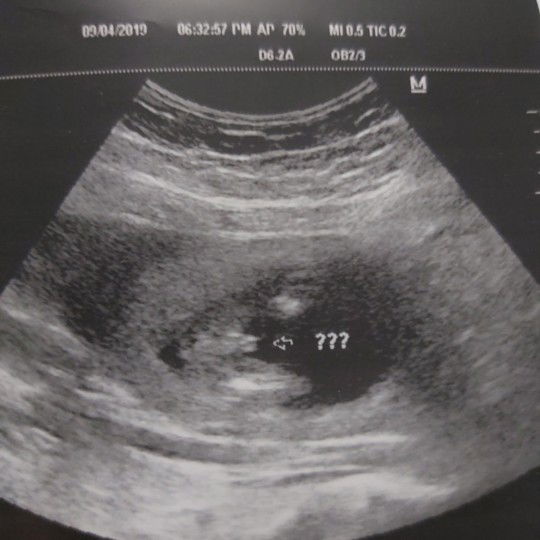

BOY OR GIRL?

Hi mga Momsh, what do you think po, baby girl or baby boy? Sabi po ng ob ko, mukhang lalaki pero di daw sya 100% sure kaya may mga question marks pa. Hehehe. Sa tingin niyo po mga momsh? FTM here. Thank you po

Repeat ultrasound po after a month to make sure. We have several cases na ganyan. Un pala umbilical cord..

boy po..ganyan din sa baby ko eh..hehe may lawit..

Boy po may lawit ei

Boy may lawit e😍